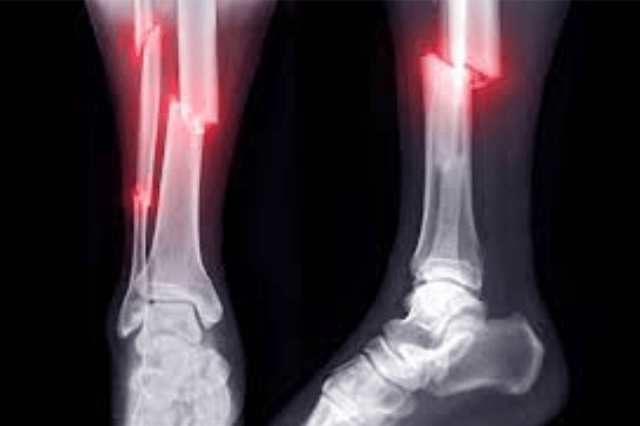

Fractures can be painful and require immediate attention. Our fracture clinic at Medilife Superspeciality Clinic Punawale is equipped with the latest technology and equipment to provide accurate diagnosis and effective treatment for fractures. Our team of orthopaedic specialists ensures that you receive the best possible care and treatment for your fracture, whether it requires casting, splinting, or surgery.